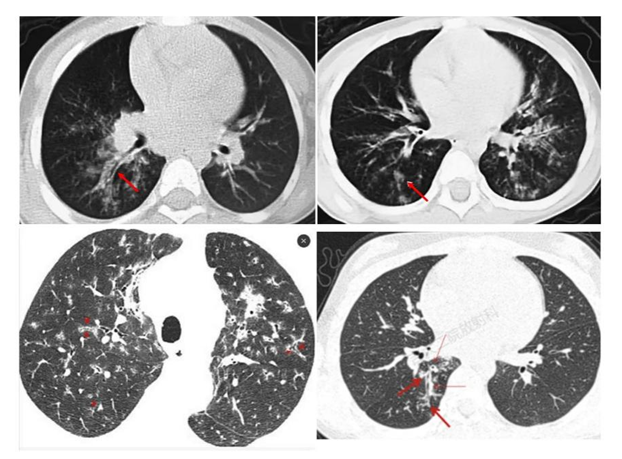

影像学检查尤其是CT是重要的检查手段,也是临床判断病情严重程度和评估预后的主要依据之一。支原体肺炎病理变化是首先侵犯气道粘膜上皮,引起支气管壁水肿增厚,接着向气道周围间质蔓延,引起肺间质充血、水肿及炎性细胞浸润,最后延伸至肺泡。在CT图像上主要有以下几种表现:

1.支气管壁增厚:支气管肺炎较可靠征象,支气管壁光滑、均匀增厚,可侵犯周围间质,周围边缘模糊,表现为支气管炎及周围炎,多由肺门向外周进展。

2.树芽征:细支气管或终末支气管内粘液阻塞,远端增粗,像树上发的新芽。

3.树雾征:支气管周围间质水肿,形成沿支气管蔓延的磨玻璃影,如同树周围的雾一样。

4.磨玻璃影:间质内水肿或部分肺泡内渗出,表现为磨玻璃样影。

5.大片实变:表现为中-高密度阴影,可有支气管气象,可伴有肺不张及胸腔积液,早期可表现为小叶中心结节影,随着病灶进展,进展为全小叶或更大范围。

随诊疾病的不同阶段,多种形态、大小不等和密度不均的病灶可混合出现,支气管壁增厚、树芽征、树雾征及实变影等征象可同时存在,结合咳嗽、发热等症状,可对支原体肺炎做出诊断。